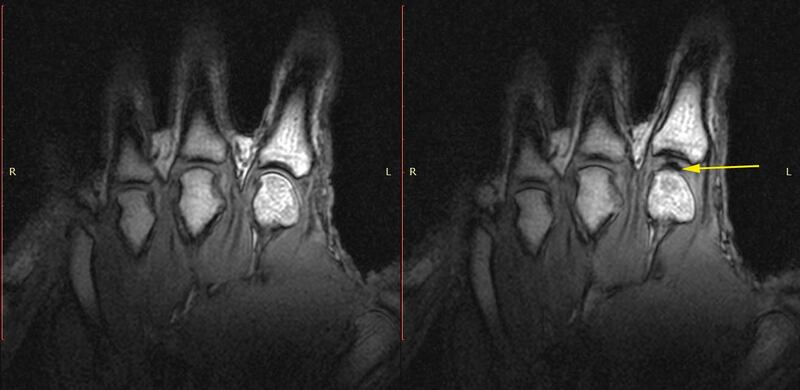

In 2015, however, Greg Kawchuk of University of Alberta and collaborators used an MRI scanner to record what was happening in the finger of a volunteer who was a frequent knuckle-cracker.

In the images, you can see the sudden appearance of a bulge in the knuckle as it is cracked.

This is the result, Kawchuk and colleagues wrote, of the formation a bubble, which persisted for some time afterward, and whose creation might be responsible for the cracking noise. They posited that the bubble generated a pressure wave in the fluid, producing a sound. However, it was not clear how that wave could be powerful enough to make the distinctive crack.